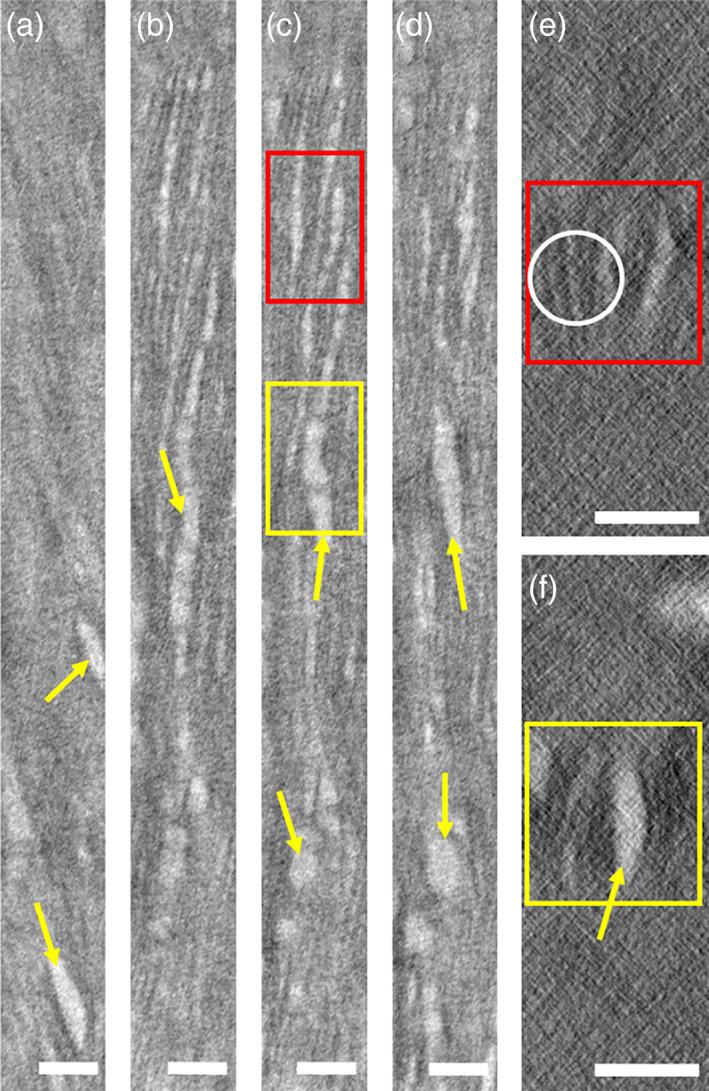

Bone is a complex natural material with a complex hierarchical multiscale organization, crucial to perform its functions. Ultrastructural analysis of bone is crucial for our understanding of cell to cell communication, the healthy or pathological composition of bone tissue, and its three-dimensional (3D) organization. A variety of techniques has been used to analyze bone tissue. This article describes a combined approach of optical, scanning electron, and transmission electron microscopy for the ultrastructural analysis of bone from the nanoscale to the macroscale, as illustrated by two pathological bone tissues. By following a top-down approach to investigate the multiscale organization of pathological bones, quantitative estimates were made in terms of calcium content, nearest neighbor distances of osteocytes, canaliculi diameter, ordering, and D-spacing of the collagen fibrils, and the orientation of intrafibrillar minerals which enable us to observe the fine structural details. We identify and discuss a series of two-dimensional (2D) and 3D imaging techniques that can be used to characterize bone tissue. By doing so we demonstrate that, while 2D imaging techniques provide comparable information from pathological bone tissues, significantly different structural details are observed upon analyzing the pathological bone tissues in 3D. Finally, particular attention is paid to sample preparation for and quantitative processing of data from electron microscopic analysis.